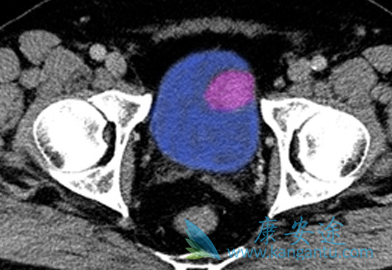

Tecentriq(atezolizumab)是一种程序死亡配体1(PD-L1)阻断抗体,适用为有局部晚期或转移尿路上皮癌患者的治疗患者(含铂化疗期间或后有疾病进展;用含铂化疗新辅助或辅助治疗12个月内有疾病进展)。Tecentriq的安全性和有效性透过一项纳入310例局部晚期或转移性尿路上皮癌的单臂临床研究进行了评价。

总体上,肿瘤出现全部或部分缩小的患者比例(客观应答率)为14.8%,该作用可持续2.1~13.8个月。PD-L1表达阳性患者,应答率提高至26%,这表明PD-L1表达水平有助于医生识别哪些患者可能从Tecentriq治疗中获益更大。因此FDA同时批准了Tecentriq辅助诊断试剂Ventana PD-L1(SP142)分析试剂盒。